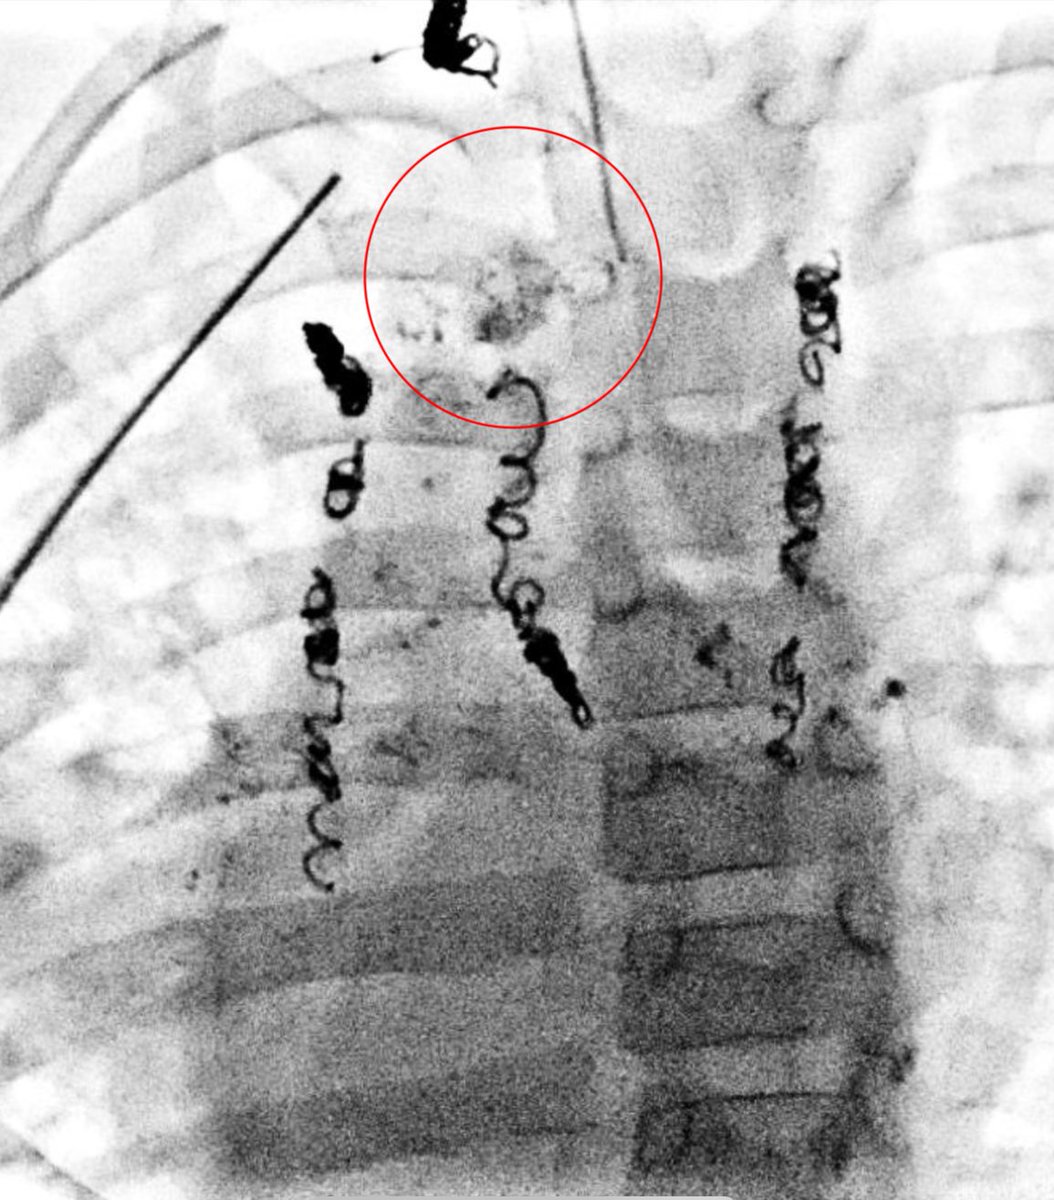

Centro interdisciplinario de anomalías vasculares CIAV del sanatorio Materdei, un orgullo formar parte de este equipo . Consultas ciavmaterdei@gmail.con #anomaliasvasculares #hemangiomas

Pediatric Interventional Radiologist. #pedsir #vascularanomalist #Anomaliasvasculares. Chief of Clinic at Garrahan Hospital and Materdei Clinic @PEDimage